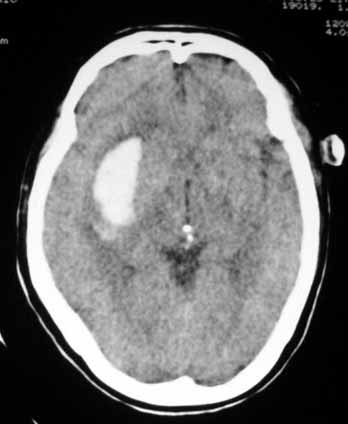

以下是引用jinning在2007-5-26 21:17:00的发言:[br]1、右侧外囊区脑出血[br]2、左侧额叶囊样低密度影,邻近颅骨内板见有骨质破坏,结合病史,符合转移瘤

以下是引用sjing在2007-5-26 21:17:00的发言:[br]1、右侧外囊区脑出血[br]2、左侧额叶囊样低密度影,周围结构无负占位效应,邻近颅骨内板见有骨质破坏,结合病史,考虑转移瘤.建议增强检查

以下是引用xinhai18在2007-5-26 20:15:00的发言:[br]1、右侧外囊区脑出血[br]2、左侧额叶囊样低密度影,邻近颅骨内板见有骨质破坏,结合病史,符合转移瘤.